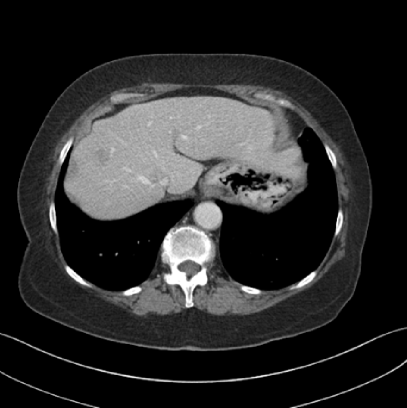

Finally, we tested the qualitative clinical results of JENG on 5 thoracic and 3 abdominal scan datasets in terms of spatial resolution, artifacts, image noise and low-contrast detectability. All clinical scans were retrospective and were acquired during routine clinical practice at a major children’s hospital in the United States. All thoracic scans used the same settings as in the ACR phantom scans, except that the tube current was modulated differently for each patient based on their body thickness, weight, and age. The abdominal scans, however, had a reduced helical pitch at 0.6 to improve low contrast lesion detectability. For all clinical images in this paper, the clinical standard hybrid IR used a soft tissue high-contrast kernel for reconstructions and we compared the image noise and artifacts of JENG and the clinical standard hybrid IR after we matched their spatial resolution.

Figure 14: Qualitative clinical results from a thoracic CT staging dataset for a 12-year-old with osteosarcoma with pulmonary metastases. The clinical standard hybrid IR is shown on the left and JENG is on the right. (a) The clinical standard hybrid IR in lung window with a window center of -600 HU and a window width of 1500 HU. (b) JENG at a resolution comparable to the clinical standard, but with less noise and fewer artifacts. (c) The clinical standard hybrid IR in soft tissue window with a window center of 55 HU and a window width of 440 HU. A metastatic lung cancer nodule can be found in the left upper lobe. (d) JENG in soft tissue window at a comparable resolution, but with less noise and fewer artifacts. Note that JENG is not fully corrected for beam hardening artifacts.

V.B. Clinical Cases

None of the spatial resolution and artifact reduction advantages would hold unless JENG shows image quality improvement over the clinical standard method on patient datasets. To do so, we evaluated JENG on 5 thoracic and 3 abdominal CT scans and all scans used the same parameter settings as those for the ACR phantom scan, except that the tube current and the pitch is modulated individually for each patient. The exact experiment setup was discussed in Sec. IV.. For a fair image quality comparison, we matched the resolution of JENG and the clinical standard hybrid IR and studied their image noise and artifacts.